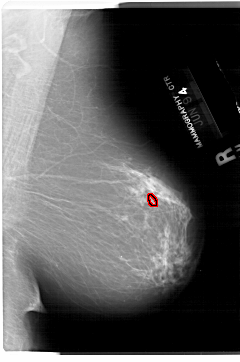

A_1503_1.RIGHT_MLO

RIGHT_MLO LINES 6871 PIXELS_PER_LINE 4546 BITS_PER_PIXEL 12 RESOLUTION 43.5 OVERLAY

FILE: A_1503_1.RIGHT_MLO.OVERLAY

TOTAL_ABNORMALITIES 1

ABNORMALITY 1

LESION_TYPE CALCIFICATION TYPE PLEOMORPHIC DISTRIBUTION LINEAR

ASSESSMENT 4

SUBTLETY 2

PATHOLOGY MALIGNANT

TOTAL_OUTLINES 1

BOUNDARY